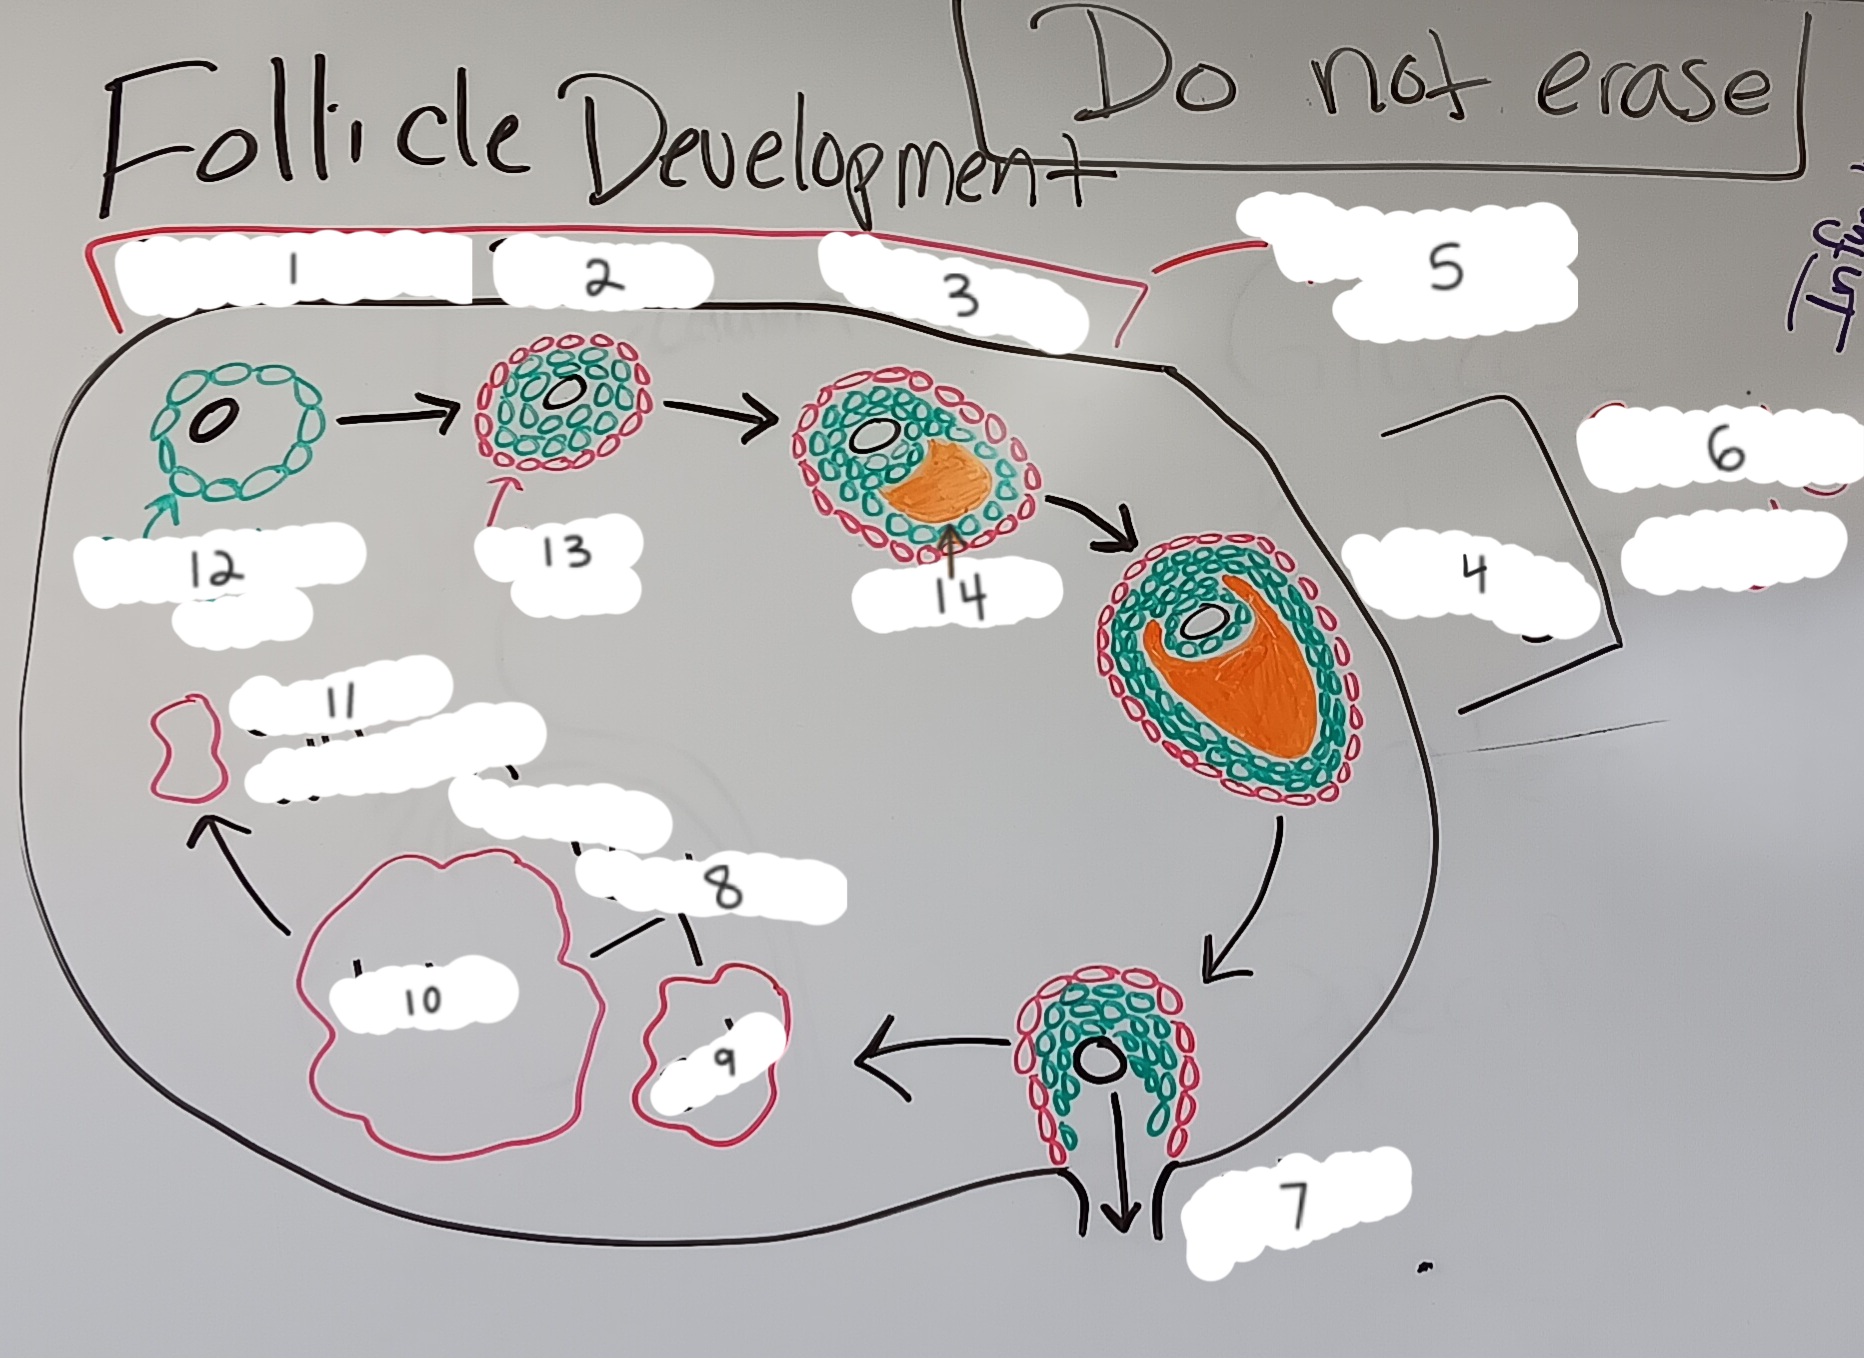

Primordial follicle

1

Primordial follicle

Primordial follicle

1

Primary follicle

2

Primary follicle

Primary follicle

2

Secondary follicle

3

Secondary follicle

Secondary follicle

3

Tertiary follicle

4

Tertiary follicle

4

Mature follicle

5

Mature follicle

Mature follicle

7

Antrum

10

Zona pellucida

9

Theca folliculi

8

Corona radiata

Corpus luteum

Corpus luteum

Corpus albicans

Corpus albicans

corpus luteum

8

early corpus luteum

9

late corpus luteum

10

corpus albicans

11

granulosa cells

12

theca cells

13

antrum

14